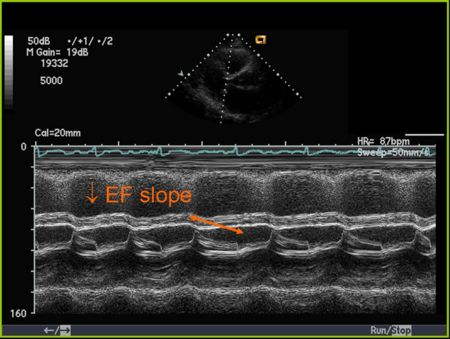

M Mode in Mitral Stenosis

- Leaflet tips bright (calcified) and thickened

- E/F slope decreased